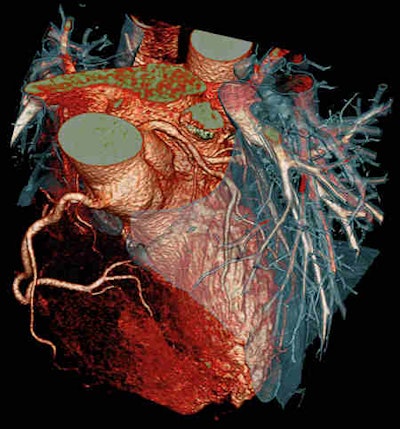

Cardiac CT images look stunning, but the technique is not perfect. This CT scan used the Flash Spiral Cardio facility of the Somatom Definition system. A 0.9 mSv dose was needed to show the fine details. Image courtesy of Siemens Healthcare.Meier concedes CT radiation levels have been greatly reduced, but the images produced at 5 mSv do not lead to diagnostic confidence. As a result, patients often undergo a nuclear perfusion study at 9 mSv or possibly even a second examination to validate findings.